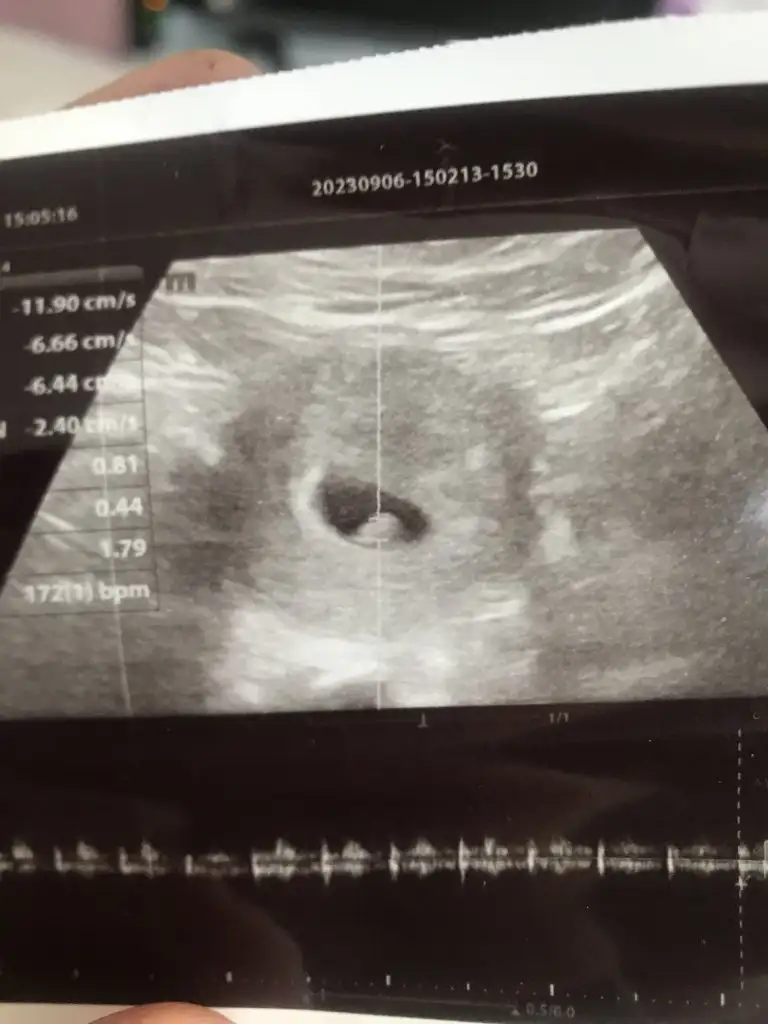

Merhaba bence kız, sağlıkla gelsin inşallahBizi de yorumlarmısınız 6+6 günlük vajinal usg

Merhaba cinsiyeti öğrendiniz mi benim ultrasonda aynı merak ettimBizi de yorumlarmısınız 6+6 günlük vajinal usg